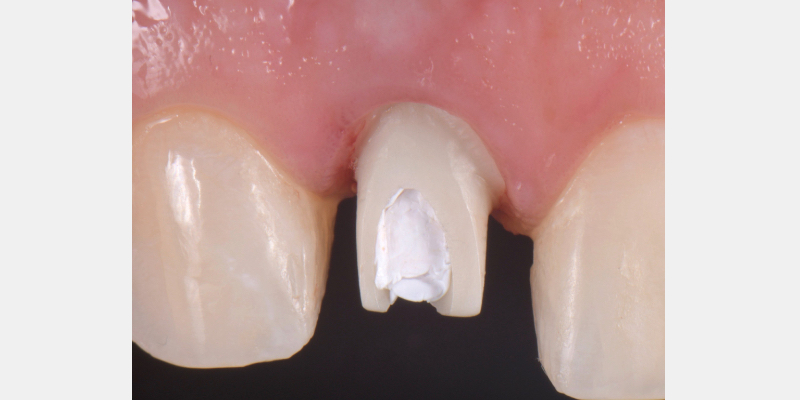

Here is a simple, step-by-step technique for fabricating a silicone jig to avoid excess cement in a cement-retained implant-supported restoration. It can be applied to a single crown or to an implant-supported cement-retained bridge.